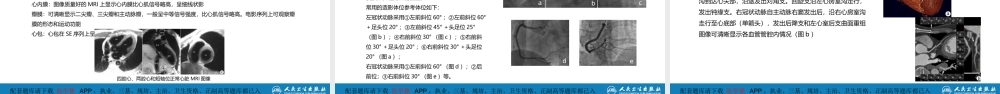

目录配套题库请下载医学猫APP,执业、三基、规培、主治、卫生资格、正副高等题库都已入库配套题库请下载医学猫APP,执业、三基、规培、主治、卫生资格、正副高等题库都已入库作者:吕滨于薇冉海涛单位:中国医学科学院阜外医院首都医科大学附属北京安贞医院重庆医科大学附属第二医院第五章循环系统目录配套题库请下载医学猫APP,执业、三基、规培、主治、卫生资格、正副高等题库都已入库第一节检查技术第二节正常影像表现配套题库请下载医学猫APP,执业、三基、规培、主治、卫生资格、正副高等题库都已入库重点难点熟悉了解掌握循环系统的正常影像学表现循环系统的检查技术各种影像检查技术在循环系统应用的适应证和优缺点配套题库请下载医学猫APP,执业、三基、规培、主治、卫生资格、正副高等题库都已入库检查技术第一节配套题库请下载医学猫APP,执业、三基、规培、主治、卫生资格、正副高等题库都已入库医学影像学(第8版)检查技术一、X线检查二、超声检查三、CT检查四、MRI检查配套题库请下载医学猫APP,执业、三基、规培、主治、卫生资格、正副高等题库都已入库(一)心脏摄片优点:直观显示肺循环情况,判断肺血多少和肺淤血程度,对心腔大小作出初步判断缺点:不能直接显示心腔和血管内的病变一、X线检查(二)心导管术和心血管造影优点:心导管检查是测量肺动脉压力、跨压力差、计算全肺阻力、肺毛细血管嵌顿压等的“金标准”冠状动脉造影是判断冠状动脉狭窄程度的“金标准”缺点:有创检查医学影像学(第8版)(三)经导管血管腔内成像技术(血管内超声和光学相干断层成像)优点:显示冠状动脉斑块、冠状动脉内支架贴壁情况、判断易损斑块的最佳技术缺点:有创检查,价格昂贵,无法在临床常规开展配套题库请下载医学猫APP,执业、三基、规培、主治、卫生资格、正副高等题库都已入库医学影像学(第8版)二、超声检查优点:方便、安全、实时,为循环系统首选影像检查技术,可直观显示各心腔大小、瓣膜病变(包括反流及狭窄)情况,测量跨瓣压差、峰值流速,明确心内结构异常,异常分流等,是各类心脏病尤其是先天性心脏病和瓣膜性心脏病最重要的检查方法缺点:有时心脏成像受肺部气体干扰而影响检查效果,尤其是肺气肿病人;术后卧床病人由于声窗有限,影响检查效果;对于心外病变评价受限配套题库请下载医学猫APP,执业、三基、规培、主治、卫生资格、正副高等题库都已入库医学影像学(第8版)二、超声检查二维超声心动图:直观、实时动态...